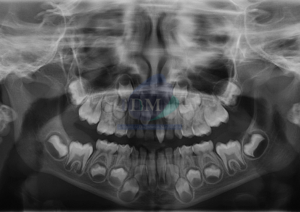

Paciente femenino de 13 años de edad, es referido al Instituto de Diagnóstico Maxilofacial – IDM para evaluación general. En la radiografía panorámica (Figura 1),

Paciente masculino de 16 años de edad, es referido al Instituto de Diagnóstico Maxilofacial – IDM para evaluación general. En la radiografía panorámica (Figura 1),

Paciente femenino de 10 años de edad, es referido al Instituto de Diagnóstico Maxilofacial – IDM para evaluación general. En la radiografía panorámica (Figura 1),